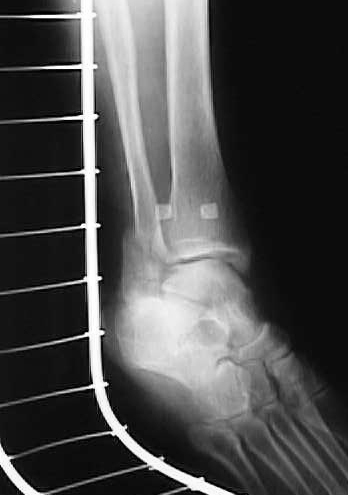

4月8日再度X線撮影(図9、10)。医師のX線写真の結果報告により骨の位置にほぼ問題がないと判断する。

図9

図10